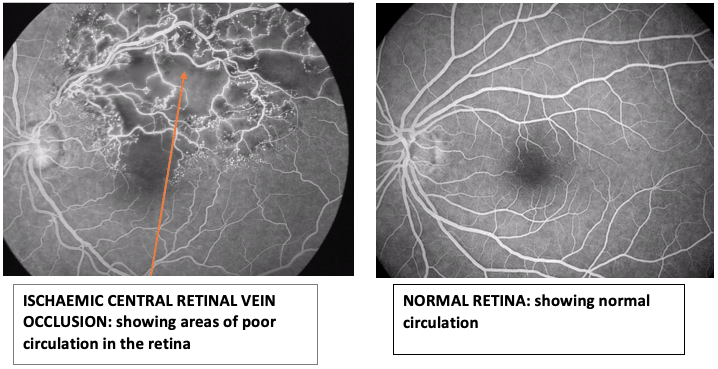

What is a Central Retinal Vein Occlusion (CRVO)?

The eye’s retina has arteries and veins which carry blood to and out of the eye. The retinas has one main artery and one main vein.

A central retinal vein occlusion is when the main vein of the retina is blocked. This causes blood and fluid to seep out into the retina.

The macular (central part of the retina) can also become swollen due to this blockage and cause distortion in central vision.

Not all CRVO cases need active treatment and may only require observation. This is especially if the blood flow is not severely compromised. This type of central retinal vein occlusion is called a non-ischaemic CRVO.

In other cases, the blood flow is significantly blocked and this leads to poor circulation to the retina. This type of central retinal vein occlusion is called a ischaemic CRVO. In ischaemic CRVO, laser to the retina called panretinal photocoagulation is needed to reduce the oxygen requirement of the retina. This is needed to prevent abnormal blood vessels from growing in a process called neovascularization. Neovascularization can lead to serious complications such as vitreous haemorrhage (bleeding in the eye) and glaucoma (high eye pressure).